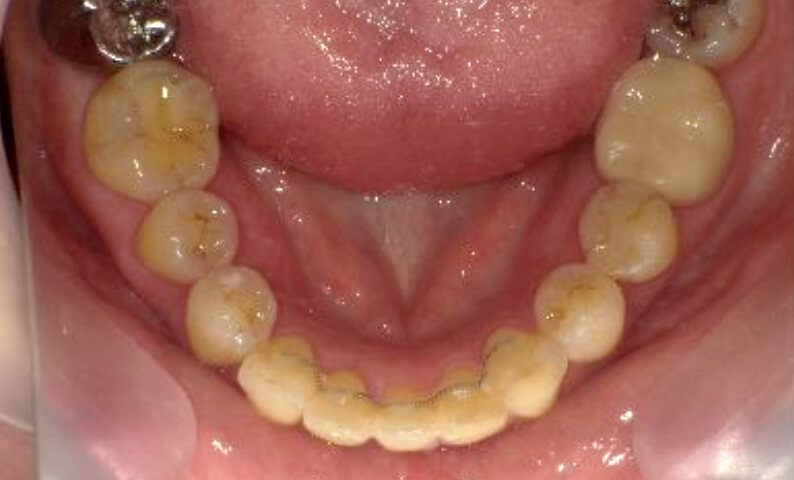

症例_003 下顎だけの部分矯正

治療期間:10ヶ月金額:24万円+税女性前歯のガタガタ下の前歯だけ上顎は補綴治療中

| Before | After |